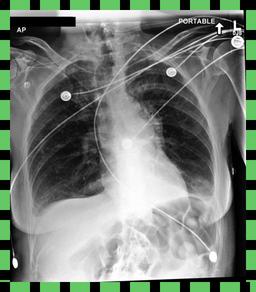

Curation of imaging datasets

CXR datasets [36] often contain multiple image acquisitions in a single visit due to data quality issues such as a limited field-of-view or scanning the wrong body part (Figure A.7). Unlike [9, 32, 81], we conduct curation to choose higher quality images among the potential candidates instead of performing a random selection. For this step, a separate BioViL-T is trained on ‘clean’ studies with single acquisitions and later used in a zero-shot setting to detect out-of-distribution samples [26, 27] arising from the re-imaging process. The candidate is selected as follows: for a margin . This approach is applied to enhance the quality of the temporal classification dataset given its limited size.

A.4 Data curation of imaging datasets

Large datasets often contain instances that are mislabelled or out of distribution [35]. We used BioViL-T to perform pairwise ranking of instances in MIMIC-CXR (Section 3.3, ) and selected representative examples found in the dataset. Our method is able to select the most appropriate image for a range of different image-acquisition or image-processing issues (Figure A.7).

We found that many lateral acquisitions in the dataset were unexpectedly labelled as frontal (Figure 7(a)). Some images contained only noise (Figure 7(b)), non-human samples (Figures 7(d) and 7(e)) or incorrect anatomy (Figure 7(g)). Often, acquisitions with an incomplete field of view (FOV) (i.e., the lungs are not completely visible) were repeated (Figure 7(c)). Lastly, post-processed images were detected by the algorithm such as contrast-enhanced scans (Figure 7(i)) that are not often used for diagnostic purposes in clinical practice.